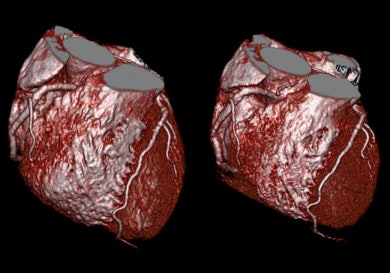

![]() |

| Patient admitted with atypical chest pain under exertion. A six-second cardiac CT scan was performed to rule out coronary artery disease. Heart rate during the scan varied from 79-86 beats per minute. Images demonstrate comparison of the right coronary artery in diastole and systole. The right coronary shows the highest range of motion during the cardiac cycle, and therefore can be difficult to capture. The CT images above are displayed clearly without motion artifacts in both phases. Images courtesy of Siemens Medical Solutions. |